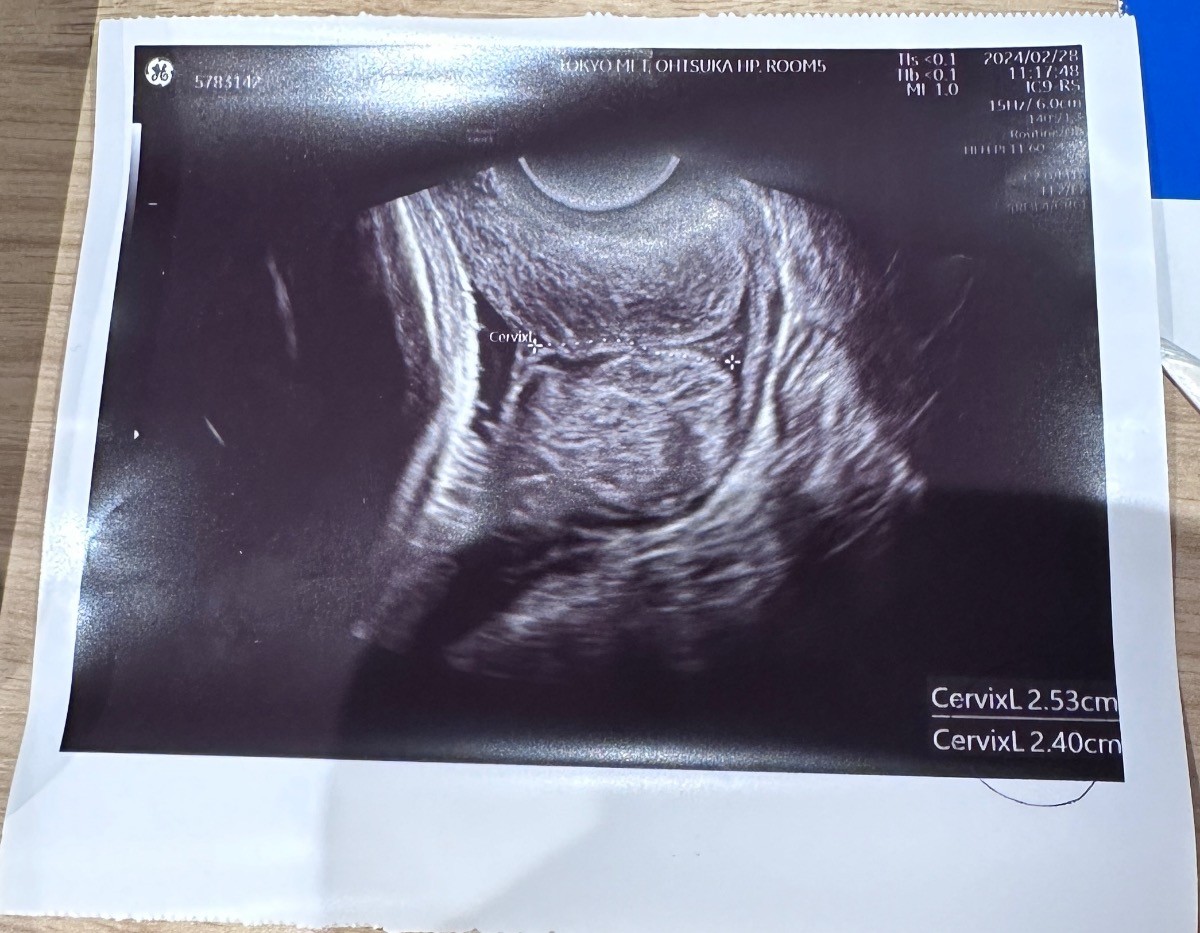

Chào add. Hiện tại m đang ở tuần thứ 29w6d, thì khi đi khám bác sỹ đo cổ tử cung là 2.53cm, và được cho là bị ngắn. Mình muốn hỏi là trường hợp mình muốn đi máy bay thì có nguy hiểm không ạ?( hiện tại m đang ở nc ngoài, muốn về vn để sinh)

Trong trường hợp cổ tử cung ngắn thì mẹ bầu nên hạn chế đi lại, vận động và thay đổi tư thế đột ngột. Trên thực tế, không phải mẹ bầu nào cổ tử cung ngắn cũng sinh non, tuy nhiên việc di chuyển bằng máy bay với chặng đường dài và đi bộ nhiều, kèm theo lo lắng về mặt tâm lý có thể làm tăng nguy cơ. Và để đảm bảo an toàn cao nhất cho mẹ và bé, Mamibabi khuyên bạn nên sinh tại nước hiện nay bạn đang sinh sống. Trong trường hợp vẫn muốn bay về VN, bạn nên xin ý kiến bác sĩ đã trực tiếp khám thai cho mình để được tư vấn chi tiết nhất.